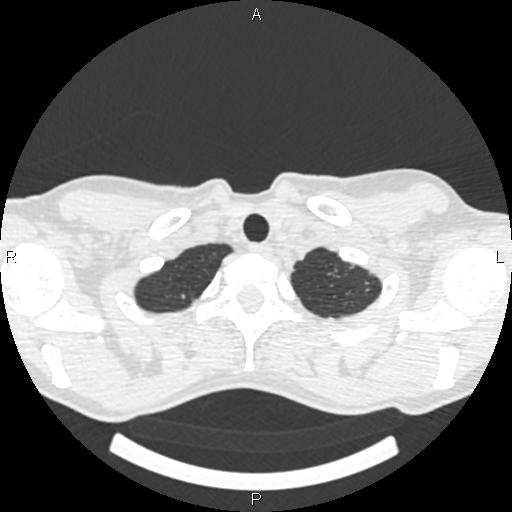

Женщина, 1975 г.р. ВИЧ инфицирована. Жалобы неспецифичны: легкое покашливание (иногда), легкое похудение. Температуры нет. Первое КТ сделано ровно 4 мес назад. Отмечались множественные...

Тип: Клиническое наблюдение

Область: Грудная клетка и верхние дыхательные пути

Модальность: КТ

Дата: 01.06.2016 - 20:47